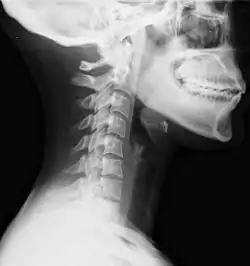

Diagnosen piskesmældsskade stilles kliniske, det vil sige ud fra sygdomshistorien og symptomerne. Der findes inden parakliniske metoder til at verificere daignosen. Røntgen eller CT-skanning af nakken bruges til, at udelukke skader på nakkesøjlen [4]. Sygdomshistorien skal indeholde en påvirkning af nakken, hvor skade på nakken er sandsynlig, fx ved en trafikulykke [5].